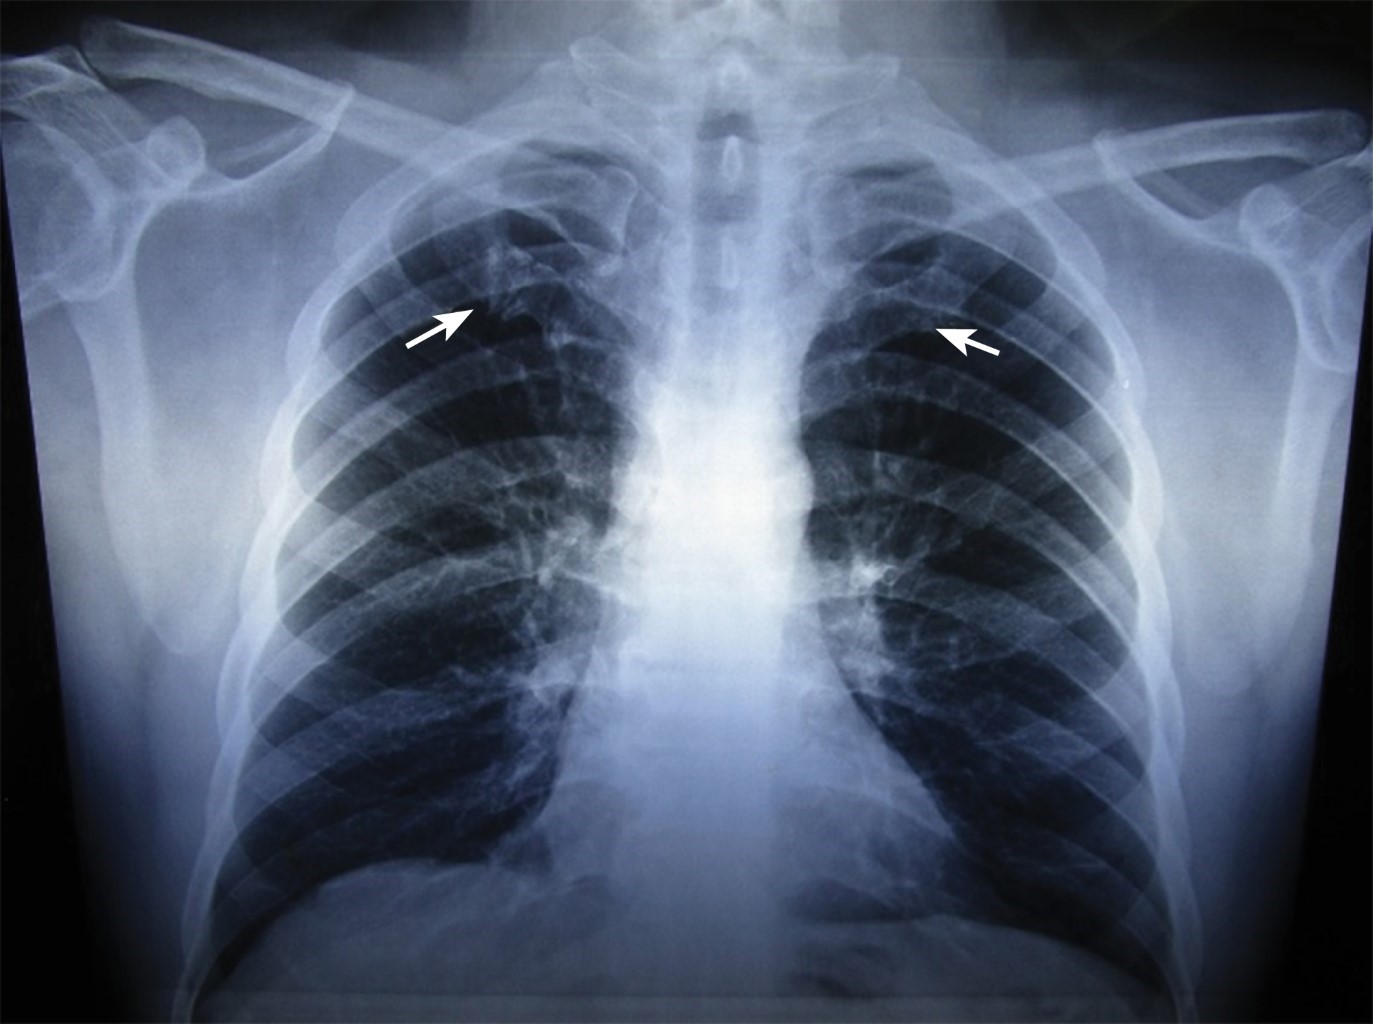

1st Costochondral Junction

1st Costochondral Junction Costochondritis Junction md explores its origins, signs, diagnosis, and remedies. The costochondral joints are joints of the thoracic wall that connect the sternal ends of the ribs and their respective costal cartilages. Costochondritis is an agonizing inflammation in the chest, often mistaken for a heart attack. They are structurally classified as primary cartilaginous joints (synchondrosis) in which bones are joined by hyaline. Costochondritis Junction.